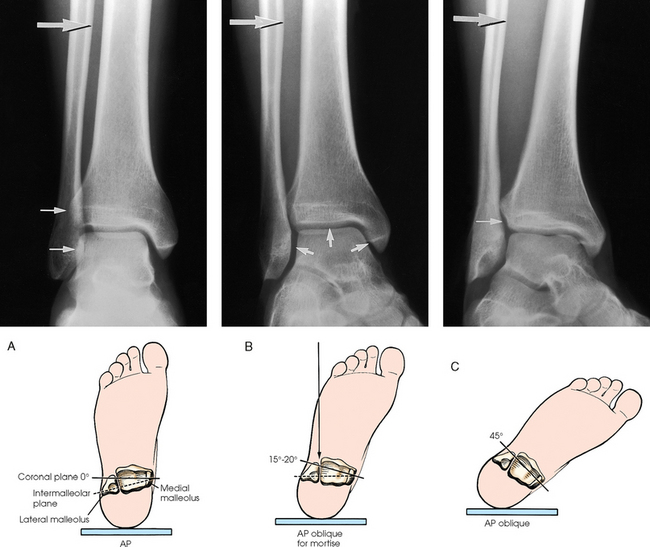

Structures shown: The resulting image shows the tibia, fibula, and adjacent joints (Fig. 6-112).

Fig. 6-112 A, AP tibia and fibula. Long leg length prevented showing entire leg. A separate knee projection had to be performed on this patient. B, Short leg length allowed entire leg to be shown. Spiral fracture of distal tibia with accompanying spiral fracture of proximal fibula (arrows) is seen. This radiograph shows the importance of including the entire length of a long bone in trauma cases. C, AP tibia and fibula on a 4-year-old with neurofibromatosis.